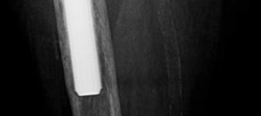

- Standard Radiographs: Anteroposterior (AP) pelvis, frog-leg lateral, and a true lateral of the affected hip are essential. These provide initial assessment of component position, subsidence, osteolysis, and general bone architecture. Stress views may be helpful for suspected pelvic discontinuity.

- This image could be a post-operative radiograph showcasing the completed reconstruction with an augment and revision cup. -

- Another post-operative X-ray providing a different view or illustrating a similar case. -

- A close-up radiographic view highlighting the augment and its screw fixation, along with the acetabular cup. -